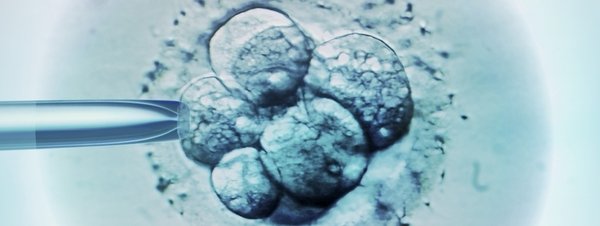

Una mujer ha quedado embarazada de los gemelos de otra pareja debido a un error de un hospital de Roma que provocó el intercambio de embriones en el proceso de fecundación in vitro. Así lo explica el diario italiano La Stampa, que señala que la unidad de reproducción e infertilidad ha sido clausurada cautelarmente y la Fiscalía romana ha abierto una investigación.

El error, al parecer, se produjo el pasado 4 de diciembre de 2013, cuando cuatro parejas diferentes estaban recibiendo tratamiento en una unidad especializada del Hospital Sandro Pertini de la capital italiana. Una de las mujeres quedó embarazada, pero de acuerdo a las pruebas genéticas, los fetos no eran compatibles con los perfiles de los padres, extremo que se conoció a los tres meses de gestación.